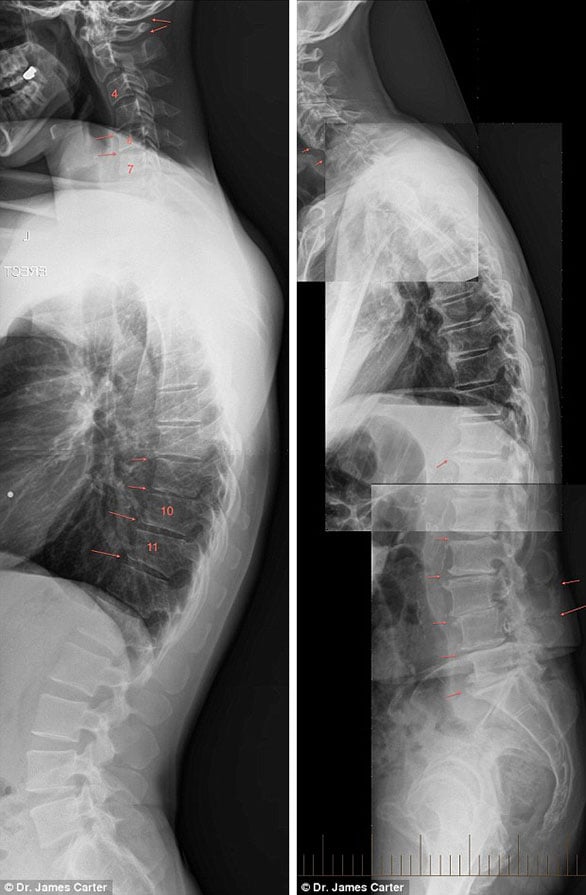

وأرفق الطبيب تحذيراته بمجموعة من صور الأشعة السينية لبعض الحالات المصابة بمرض التنكسية في العمود الفقري نتيجة استعمال الهاتف الذكي لفترة طويلة، توضح تشوهات وآلام في الرأس والرقبة والكتف والظهر.